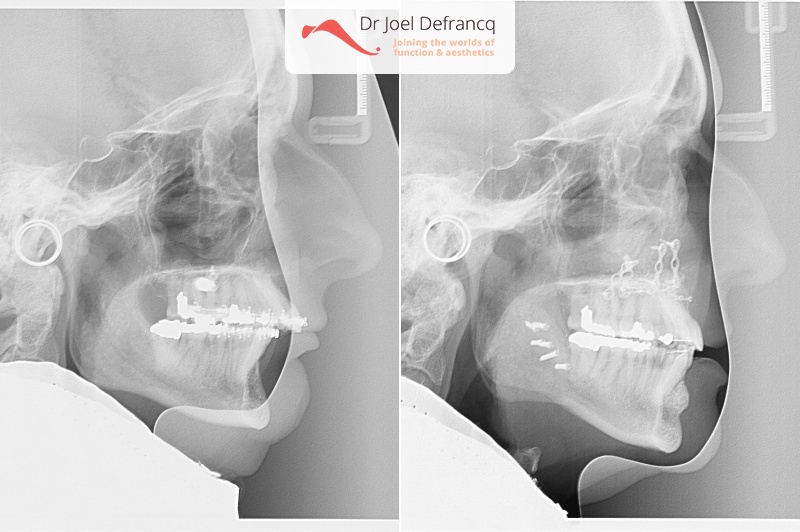

Kaakchirurgie

- Verlenging onderkaak (BSSO)

- Vertikale verlenging bovenkaak (Le Fort I)

- Verbreden bovenkaak (Smile distractor)